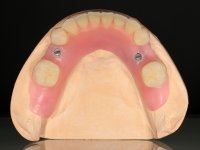

To fabricate overdentures supported and retained by milled bars screwed over the dental implants.

Then, the teeth were mounted in the screwed record bases and function and aesthetics were clinically evaluated. After these evaluations, the dental technician develops silicone walls that guide the fabrication of the milled bars. The precise passive fit of the bars was checked clinically and with radiographs. Then, a pick-up impression with an individualized tray was done to achieve a functional impression of the soft-tissues.

The overdentures with a metallic framework were fabricated over the bars, according to the silicone walls previously made. Before finishing the dentures, a new functional and aesthetic evaluation of the teeth was done, together with a new jet-bite registration to allow small occlusal adjustments.